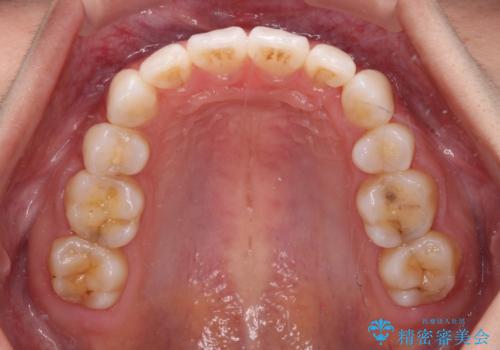

- 八重歯と口元の突出感を気にして来院された患者様です。

歯列が前方に突出しており、上下の正中がズレていたため、左側は上下第一小臼歯を、右側は上下第二小臼歯を抜去し、ワイヤー装置による矯正治療を行うこととしました。

当初はインビザラインによる矯正治療をご希望でしたが、正中を合わせたいことや、口元の突出感を改善したいことから、ワイヤー矯正を強く推奨しました。

治療期間は2年に満たず、スッキリとした口元に仕上がりました。